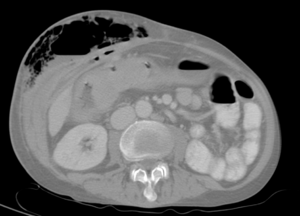

| Abdominal CT with right colocutaneous fistula and associated subcutaneous emphysema. | |

هو ناسور مكتسب غالباً يحدث تالياً لآفة أخرى، قد تكون التهابية كما في داء كرون Crohn أو داء الرتوج السينية (الرتاج) diverticulosis التي يؤدي التهابها وتشكّل خراج يلتصق بالمثانة إلى حدوث اتصال مع المثانة عبر فوهة صغيرة، أو يكون السبب ورماً في السيني sigmoid أدى تنخره إلى حدوث هذا الاتصال، كما قد يتلي التعرض للأشعة في حالة المداواة، أو ينجم عن رض جراحي بعد العمليات المجراة على الموثة (البروستات) أو القولون السيني أو المستقيم.

يتظاهر هذا الناسور سريرياً بخروج فقاعات غازية مع البول وبحدوث التهابات بولية متكررة.

يتم وضع التشخيص الأكيد عن طريق التصوير الطبقي المحوري CT.Scan.